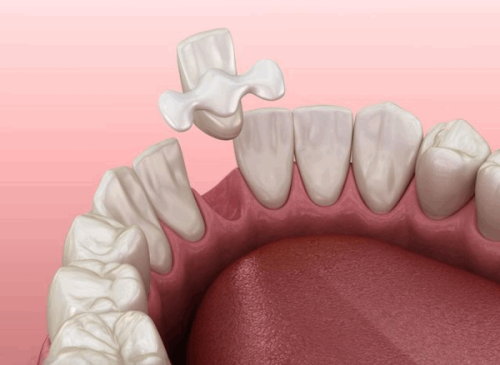

牙齿本身问题:先天的“小缺陷”

除了生活习惯,牙齿本身的状况也会影响龋齿的发生。个体之间存在差异,部分人群牙齿矿化程度较高,牙齿表面的硬度较大,较易抵御细菌的侵袭;而部分人群牙齿存在较深的窝沟,这些窝沟就像是细菌的“藏身之处”,细菌容易藏匿其中,增加了龋齿发生的几率。

对于牙齿窝沟较深的人来说,必要时可进行窝沟封闭。窝沟封闭是一种预防龋齿的有效方法,它可以将窝沟填平,防止细菌和食物残渣进入,从而降低龋齿的发生风险。